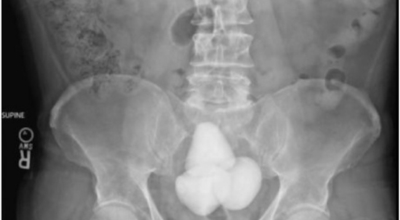

요로결석이란

수분 섭취 감소는 요로결석의 가장 주요한 발병 이유가 되는 것 이라고 하네요. 수분의 섭취가 떨어지면 요석결정이 소변에 머무르는 시간이 길어져 요석형성이 증가하게 되며 요로결석의 발생은 유전적인 소인이 있다는 것이 정설이나 후천적인 생활습관도 연관성을 보입니다.

남성이 여성에 비교해 2-3배 발생 위험성이 높고, 20~40대의 젊은 연령층에서 잘 발생하였다고 하나 최근 고령층에서 발생이 증가하고 있고 요로결석은 지리적으로 산이 많은 지역, 사막, 열대 지방에서 많이 생기는데, 이는 음식, 온도, 습도 등이 복합적으로 작용하기 때문이라고 합니다. 온도와 계절은 요로결석 발생에 주요한 요인으로 작용하지만, 여름에는 땀을 많이 흘리면서 소변이 농축되어 요로결석의 생성이 용이해진다고 합니다.